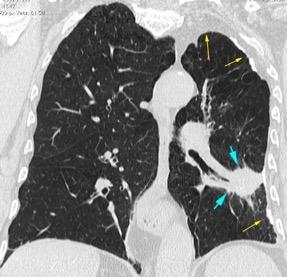

Tromboembolismo pulmonar.

Frecuencia del derrame:

Rx: 32%. TC: 47%

Unilateral. 85%

< 1/3 del hemitórax: 90%

Todos exudados

58% con eritrocitos

21% tabicación lo que causa demora en el diagnóstico

TEP. Empiema pleural. Atelectasia redonda

Porcel JM et al. Analysis of pleural effusions in acute pulmonary embolism: radiological and pleural fluid data from 230 patients. Respirology 2007/ Iguchi T et al. Desquamation of the subpleural lung parenchyma caused by empyema after pulmonary embolism: A case report. Respirol Case Rep. 2022 .